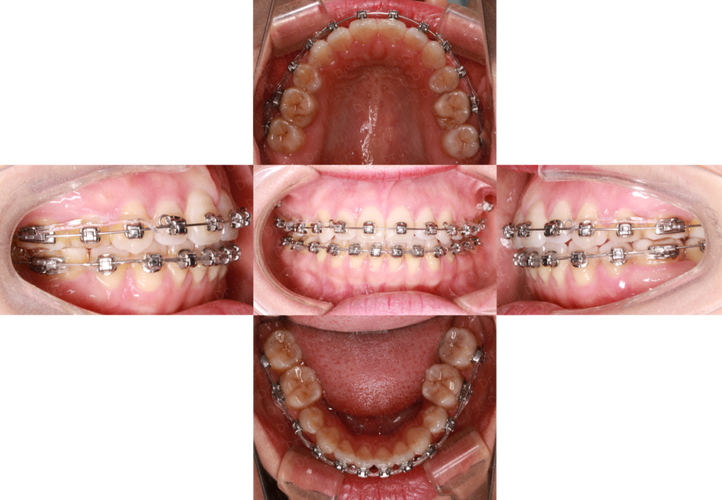

主动治疗是开合矫正的核心,需根据病因选择不同矫治器(传统金属托槽、陶瓷托槽、隐形矫治器等),分阶段完成: